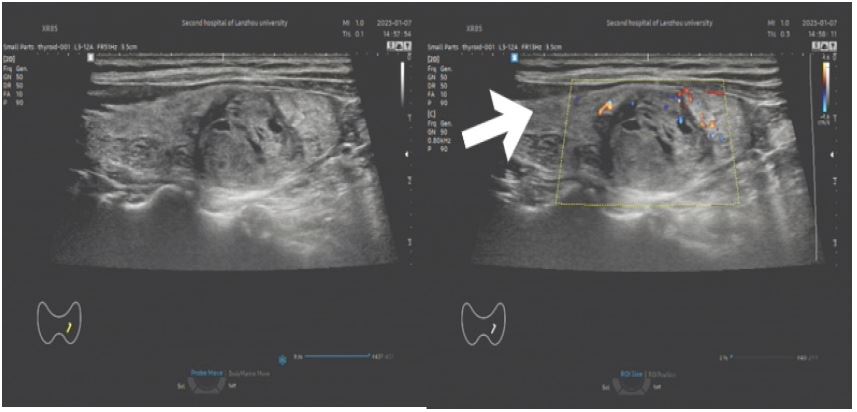

Imaging findings: 2D ultrasound revealed a 6.3 × 5.0 × 2.7 cm mixed-echo mass in the left thyroid lobe, with regular morphology, well-defined margins, heterogeneous echotexture, multiple anechoic areas, and abundant intratumoral vascularity (C-TIRADS 3). Contrast-enhanced neck CT suggested nodular goiter with possible follicular adenoma.

Figure 1: (A) A cystic solid mass of about 6.5 × 5.0 cm in size is seen in the left lobe of the thyroid gland (shown by arrows), with a regular morphology, clear borders, and heterogeneous internal echogenicity, and multiple irregular areas are seen; (B) abundant blood flow signals are seen inside and around the mass (shown by arrows).